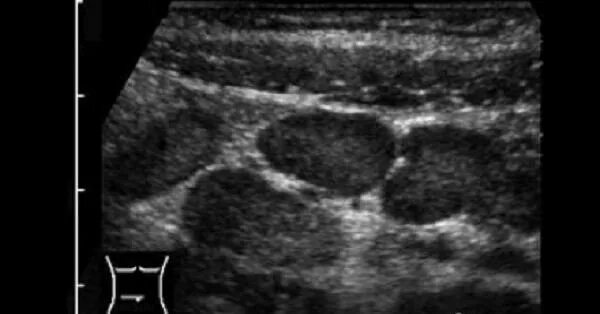

Воспаление брюшных лимфоузлов причины